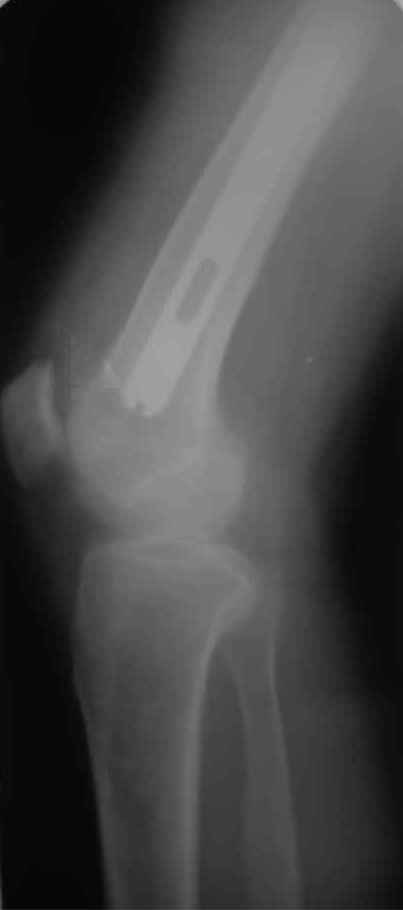

Произведено закрытое удлинение ножки эндопротеза с помощью ретроградного интрамедуллярного стержня. Продолжительность операции 3 часа. Два из них закрытое восстановление длины бедра диистрактором

таз-бедро.

А нельзя ли увидеть и профиль бедра на всем протяжении, т.е. и весь протез, и весь стержень? И фас бы с коленом.

новые снимки